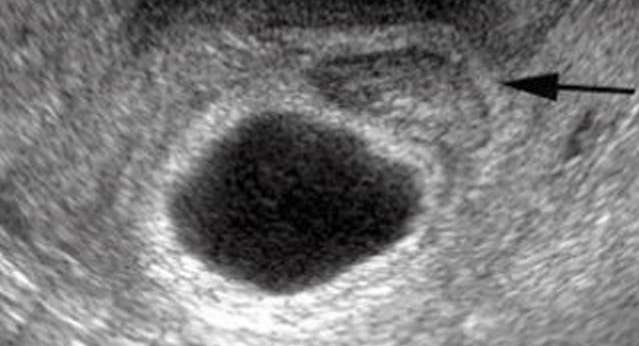

ما إن تعلم المرأة أنّ تحليل الحمل كان إيجابياً حتى ينتابها شعورٌ بالفرح والسعادة أنها تحمل في أحشائها طفلاً ستلده بعد 9 أشهر. لكن هذه الفرحة لا تتم أو لا تكتمل حين تكتشف الأم أن هذا الحمل هو كيس فارغ لا يحتوي على جنين في داخله، الأمر الذي يدفعها إلى الإجهاض. فمتى يظهر هذا كيس الحمل الفارغ وما هي العوامل التي تسبب في حدوثه؟ في البداية عندما تقوم المرأة بتحليل الحمل في المنزل ستظهر النتيجة إيجابية، طبعاً بعد التأكد من تأخّر الدورة الشهرية. لكن عند إجراء الأشعة الصوتية في الاسبوع السادس ستظهر النتائج وجود كيس حمل فارغ داخل الرحم بدون وجود جنين. حيث ستعاني المرأة بعد مرور فترة قصيرة على الحمل من نزول قطرات دم، في حين أنّ هذه القطرات قد تتحول الى نزيف غزير ما قد يستدعي الإجهاض فوراً. في حين إكتشاف أنّ كيس الحمل فارغ، ليس من الأمور النادرة الحدوث، حيث يكون كيس الحمل موجوداً كما أنّ المشيمة تعمل بشكل طبيعي، وبذلك تكون جميع أعراض الحمل مستمرة لكنك لن تعرفي بذلك قبل التأكد من خلال إجراء الصورة الصوتية.